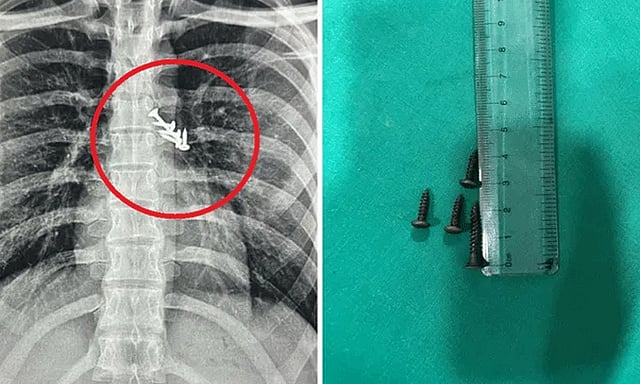

நுரையீரலில் சிக்கிய 7 ஆணிகள்.. 19 வயது இளைஞருக்கு ஷாக்

மகாராஷ்டிரா மாநிலம் பிம்பிரி மருத்துவமனையில், உறங்கிக்கொண்டிருந்த இளைஞர் தவறுதலாக விழுந்த ஆணிகளை விழுங்கிவிட்டதாக கூறி சிகிச்சைக்கு அனுமதி செய்யப்பட்டார். மருத்துவர்கள் ஸ்கேன் செய்தபோது நுரையீரல் மற்றும் வயிறு பகுதியில் ஆணிகள் இருந்தது.

உடனடியாக சுமார் 3 மணிநேர அறுவை சிகிச்சை செய்யப்பட்டு ஆணிகள் வெளியே எடுக்கப்பட்டன. இதனால் 19 வயது இளைஞரின் உயிர் காப்பாற்றப்பட்டது. மருத்துவ குழுவினருக்கு இளைஞரின் பெற்றோர் நன்றியை தெரிவித்துக்கொண்டனர்.